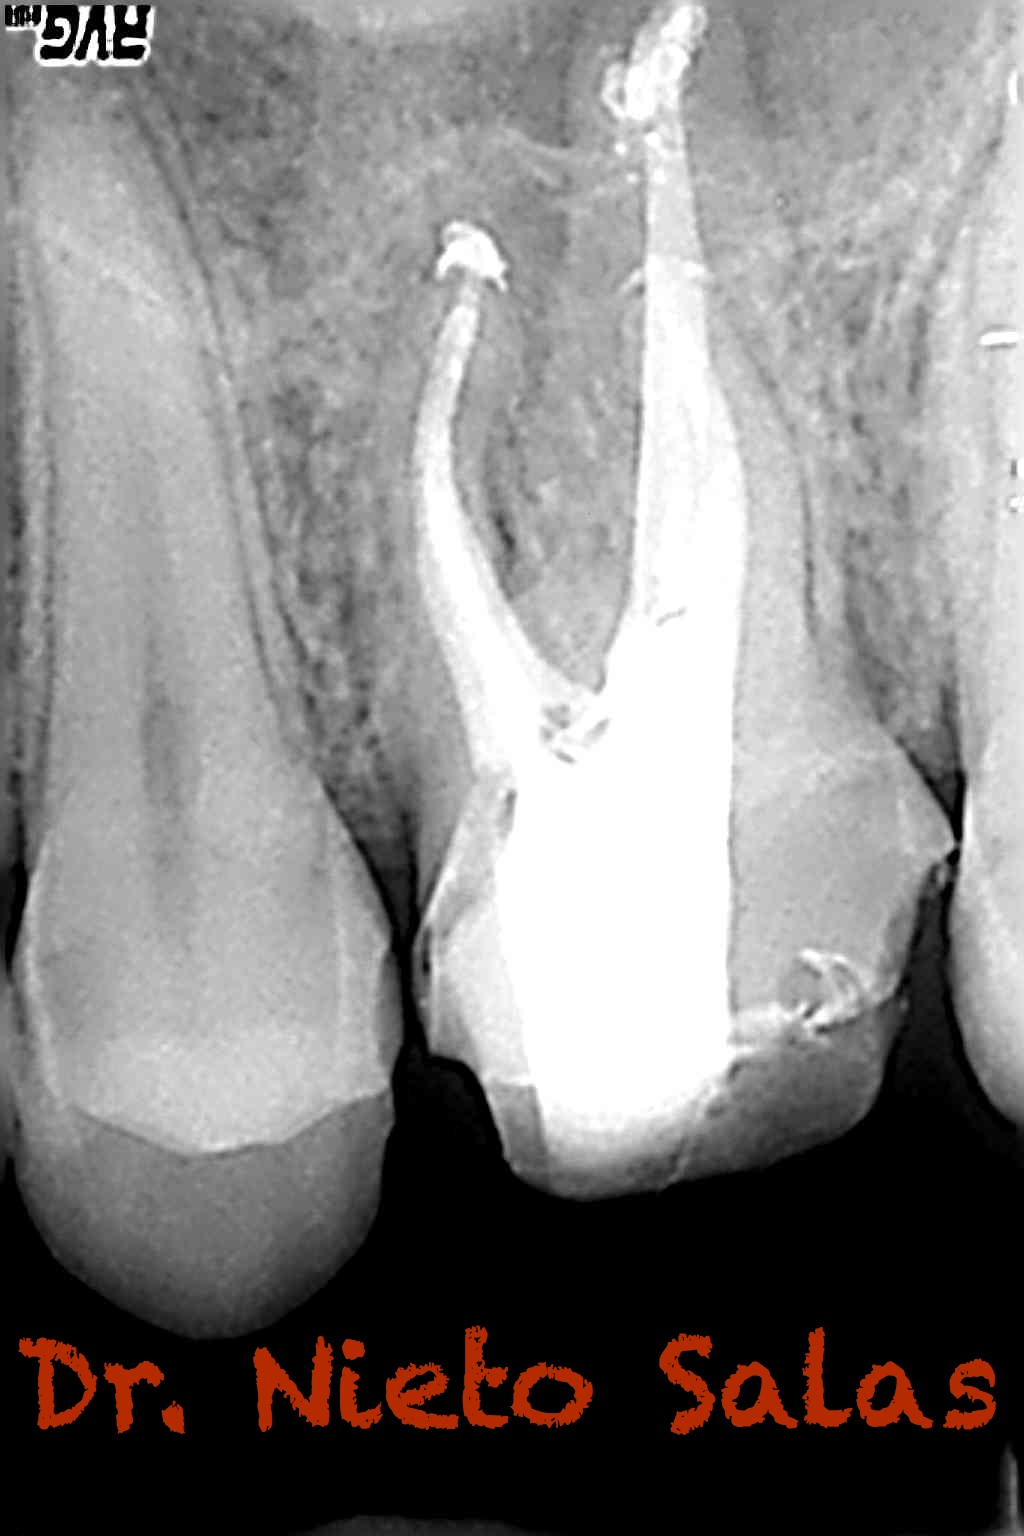

Os presento unos casos de varios molares superiores, con tres conductos mesiovestibulares con un foramen o con dos.

Una vez que tenemos medidas, obturamos los conductos:

No es habitual en nuestra práctica casos como estos, pero os pongo algunos más:

A este caso le tengo especial cariño por ser el primero que hice;